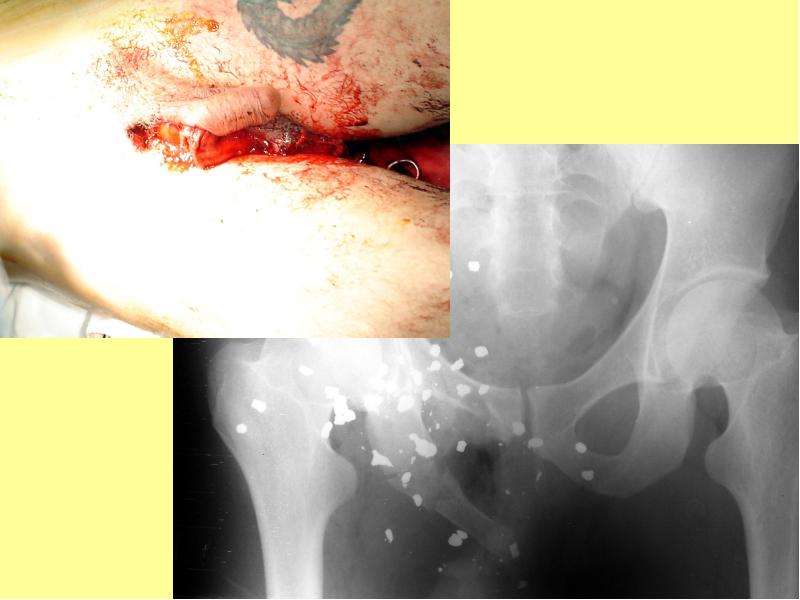

- 4. Раной называется механическое повреждение, сопровождающееся нарушением целости кожного покрова или слизистых

- 16. Скальпированная рана